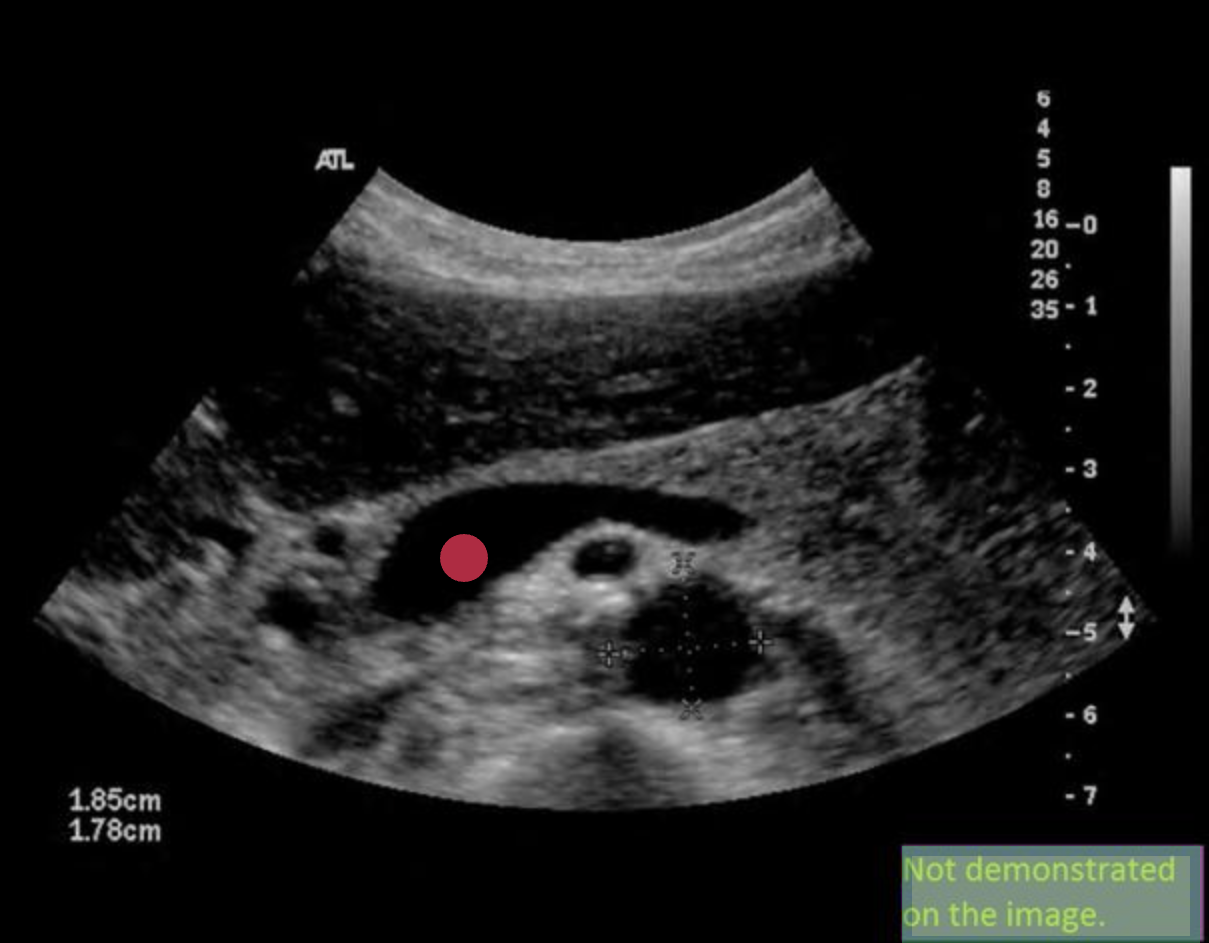

Use your mouse to place your cursor over the superior mesenteric vein and click to mark the vessel. If the vessel is not demonstrated on the image, mark the purple box that says "Not demonstrated on the image".

Use your mouse to place your cursor over the common bile duct and click to mark the vessel. If the vessel is not demonstrated on the image, mark the purple box that says "Not demonstrated on the image".